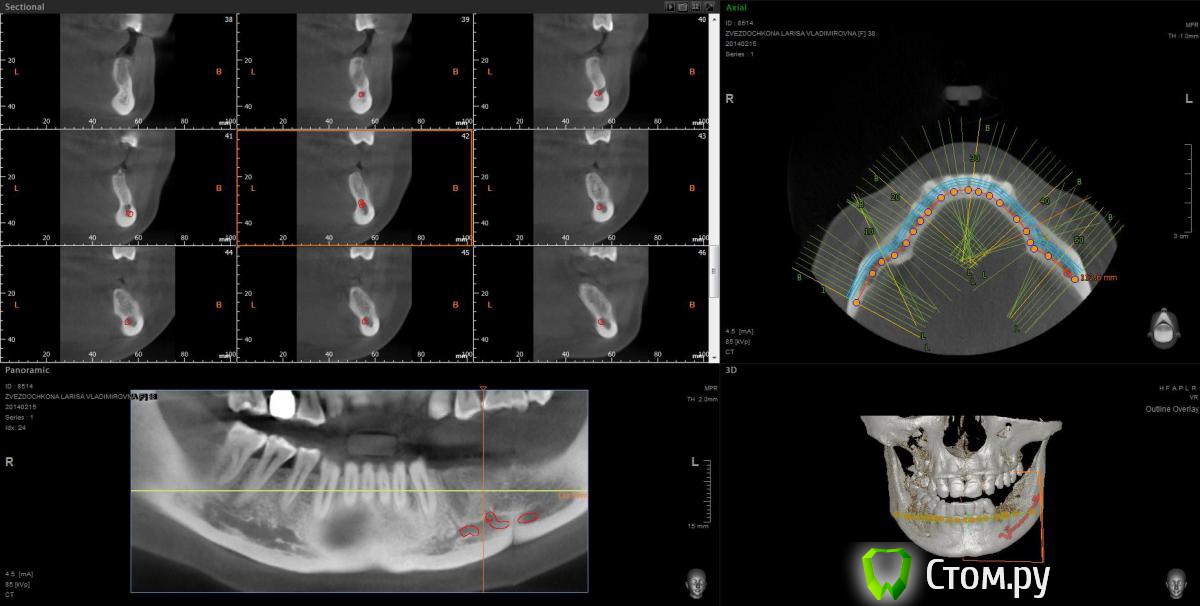

mapmax Опубликовано 3 марта, 2014 Поделиться Опубликовано 3 марта, 2014 Итак,коллеги,нуждаюсь в Вашем совете. У пациентки концевой дефект в обл 34 35 36 37, в периапикальной обл. 34 был воспалительный процесс который обострился и осенью прошлого года зуб был удален(не мной). Сейчас стоим перед имплантацией. Я рекомендую ставить импланты в обл отсутствующих зубов,но по финансовым соображениям пациентка настаивает на операции в обл 34 35 и позже в обл 36 37. Система выбрана Штрауманн SP SLActiv. Из за особенностей формы альвеолярного отростка в обл. 34 35( S-образная) и недавнего удаления 34 я рассматриваю установку импланта с язычным наклоном размера 4.8х10 RN в обл 35 RN 4.8х12. Но есть опасность оголения витков с вестибулярной стороны.Может все же сперва провести аугментацию "Аллопластом" с мембраной с вестибулярной стороны и отсрочено имплантация?! Срезы ДКТ прилагаю. Спасибо. Ссылка на комментарий